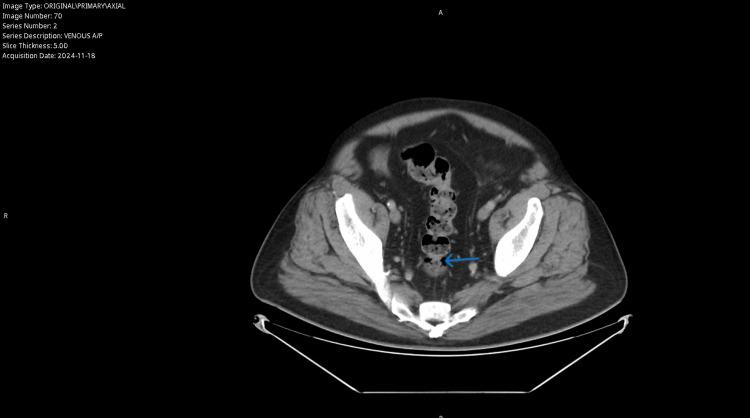

Diverticular disease and abdominal aortic aneurysms (AAAs) represent distinct but significant clinical entities often associated with advanced age. Diverticulitis, a common complication of diverticular disease, can result in perforation and systemic complications, while AAAs, frequently asymptomatic, carry substantial morbidity and mortality risks if undetected or untreated. Advances in imaging have improved the early identification of these conditions, yet the simultaneous management of both presents unique challenges requiring multidisciplinary coordination. A 67-year-old male with a history of ST-elevation myocardial infarction, hypertension, hyperlipidemia, and smoking presented with left lower quadrant abdominal pain and abnormal outpatient computed tomography (CT) findings. Imaging revealed Hinchey 1a diverticulitis with a microperforation and an incidental 6.5 cm saccular AAA. The patient received conservative treatment for diverticulitis with intravenous antibiotics and transitioned to oral antibiotics upon clinical improvement. Following resolution, the patient underwent successful endovascular aneurysm repair (EVAR) for the AAA, which was complicated by a type II endoleak identified postoperatively. Blood pressure management and hydration addressed acute kidney injury, and the patient recovered well with a multidisciplinary follow-up planned. This case underscores the importance of imaging in diagnosing coexisting conditions, particularly in high-risk populations. Management required balancing the risks of treating acute diverticulitis with the need for prompt intervention for a large, saccular AAA. The conservative approach to diverticulitis, followed by elective EVAR, reflects a patient-centered strategy consistent with current guidelines. Furthermore, it underscores the critical role of adhering to screening recommendations for high-risk populations, as timely detection of asymptomatic conditions like AAAs can prevent life-threatening complications.

憩室病和腹主动脉瘤(AAA)是不同但重要的临床实体,常与高龄相关。憩室炎是憩室病的常见并发症,可导致穿孔和全身并发症,而AAA通常无症状,如果未被发现或未得到治疗,则具有很高的发病和死亡风险。影像学的进展改善了对这些疾病的早期识别,但同时管理这两种疾病带来了独特的挑战,需要多学科协调。一名67岁男性,有ST段抬高型心肌梗死、高血压、高脂血症和吸烟史,出现左下腹疼痛,门诊计算机断层扫描(CT)检查结果异常。影像学检查显示为Hinchey 1a级憩室炎伴微小穿孔,以及一个偶然发现的6.5厘米囊状AAA。患者接受了静脉抗生素治疗憩室炎,临床改善后转为口服抗生素。症状缓解后,患者成功接受了AAA的血管内动脉瘤修复术(EVAR),术后出现II型内漏并发症。通过血压管理和补液处理了急性肾损伤,患者在多学科随访计划下恢复良好。该病例强调了影像学在诊断并存疾病中的重要性,特别是在高危人群中。管理需要平衡治疗急性憩室炎的风险与对大型囊状AAA进行及时干预的需求。对憩室炎采取保守方法,随后进行择期EVAR,体现了以患者为中心的策略,符合当前指南。此外,它强调了遵循高危人群筛查建议的关键作用,因为及时发现像AAA这样的无症状疾病可以预防危及生命的并发症。